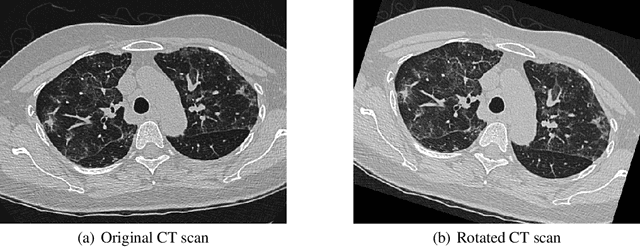

Abstract:COVID-19 has been detrimental in terms of the number of fatalities and rising number of critical patients across the world. According to the UNDP (United National Development Programme) Socio-Economic programme, aimed at the COVID-19 crisis, the pandemic is far more than a health crisis: it is affecting societies and economies at their core. There has been greater developments recently in the chest X-ray-based imaging technique as part of the COVID-19 diagnosis especially using Convolution Neural Networks (CNN) for recognising and classifying images. However, given the limitation of supervised labelled imaging data, the classification and predictive risk modelling of medical diagnosis tend to compromise. This paper aims to identify and monitor the effects of COVID-19 on the human lungs by employing Deep Neural Networks on axial CT (Chest Computed Tomography) scan of lungs. We have adopted Mask RCNN, with ResNet50 and ResNet101 as its backbone, to segment the regions, affected by COVID-19 coronavirus. Using the regions of human lungs, where symptoms have manifested, the model classifies condition of the patient as either "Mild" or "Alarming". Moreover, the model is deployed on the Google Cloud Platform (GCP) to simulate the online usage of the model for performance evaluation and accuracy improvement. The ResNet101 backbone model produces an F1 score of 0.85 and faster prediction scores with an average time of 9.04 seconds per inference.